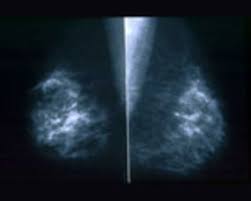

How Does Breast Cancer Look Like On A Mammogram / Mammogram Images Normal Abnormal And Breast Cancer : The outer edges of these cells look fuzzy or spiky (called spiculated).. Healthy mammograms can still vary in appearance. That makes it easy to detect abnormalities, which generally show up as white. If found in an area of rapidly dividing cells or grouped together in a certain way, they may be a sign of dcis or breast. A lump or tumor will show up as a focused white area on a mammogram. Dense breast tissue appears solid.

Breast Masses Cancerous Tumor Or Benign Lump from www.verywellhealth.com Even if you have a lump in only one breast, pictures will be taken of both breasts. This appears most commonly as streaking, known as linear enhancement. A woman's breast tissue also changes over time, and it is not uncommon for benign lumps, cysts or calcifications to form with age. Breast cancer can appear as a spiculated mass, cluster of tiny calcifications, smoothly marginated mass, area of subtle distortion or be invisible on. What does an abnormal mammogram look like? Cancer cells can remain within the milk ducts and this is considered as noninvasive cancer or ductal carcinoma in situ. Magnetic resonance imaging (mri) of the breast — or breast mri — is a test used to detect breast cancer and other abnormalities in the breast. The appearance of normal breast tissue on a mammogram varies from person to person, and no two mammograms look the same.

Mammogram Images Normal And Abnormal from www.verywellhealth.com Any area that does not look like normal tissue is a possible cause for concern. The appearance of normal breast tissue on a mammogram varies from person to person, and no two mammograms look the same. A woman's breast tissue also changes over time, and it is not uncommon for benign lumps, cysts or calcifications to form with age. What does cancer look like on a mammogram? Tumors may be benign or cancerous. Abnormalities such as cancerous tumors usually appear brighter because they are denser. Cancers may be seen as masses (like a ball, but usually with an irregular shape), areas of asymmetry that resemble normal tissue, calcifications (white specks), and/or areas of architectural distortion (imagine the puckering caused by pulling a thread in a piece of fabric). Calcifications are calcium deposits within the breast tissue and they look like small white spots.

Any area that does not look like normal tissue is a possible cause for concern. Invasive breast cancer can appear as a white patch or mass on a mammogram. You may notice dimpling or pitting, and the skin on your breast. A rash isn't the only visual symptom of inflammatory breast cancer. The milk ducts carry your breast milk from lobules, where milk is produced, to your nipple. Magnetic resonance imaging (mri) of the breast — or breast mri — is a test used to detect breast cancer and other abnormalities in the breast. A lump or tumor will show up as a focused white area on a mammogram. 1 the gray areas correspond to normal fatty tissue, while the white areas are normal breast tissue with ducts and lobes. A spiculated breast mass, which has spikes extending out from the main mass, is often highly suggestive of cancer. Macrocalcifications, which look like small white dots on a mammogram. It's so important to listen to the messages our bodies are telling. In addition to mammograms, ultrasound and mri may also be used to take a closer look at changes in the breast. Breast cancer can appear as a spiculated mass, cluster of tiny calcifications, smoothly marginated mass, area of subtle distortion or be invisible on.